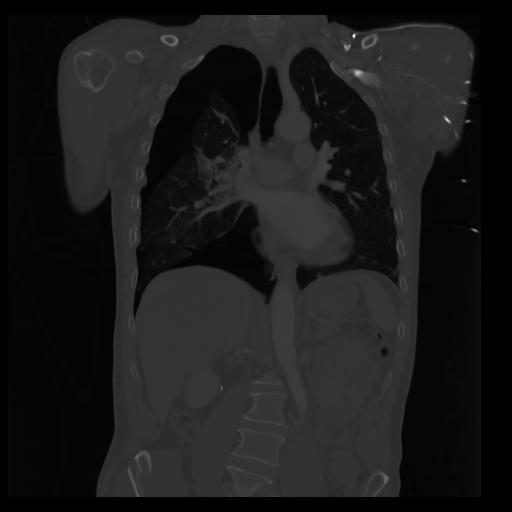

29 CUERPO,CE,Coronal,3.000,CUERPO,Coronal,